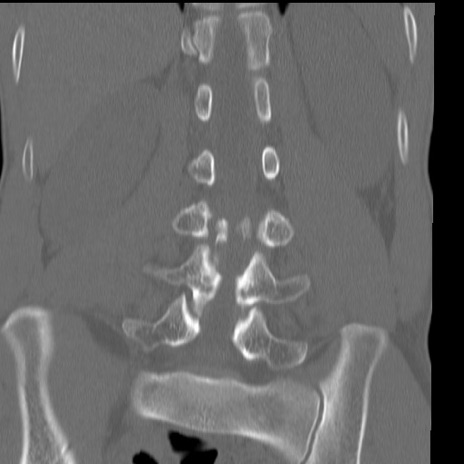

症例3 腰椎CT(冠状断像)

腰椎CT